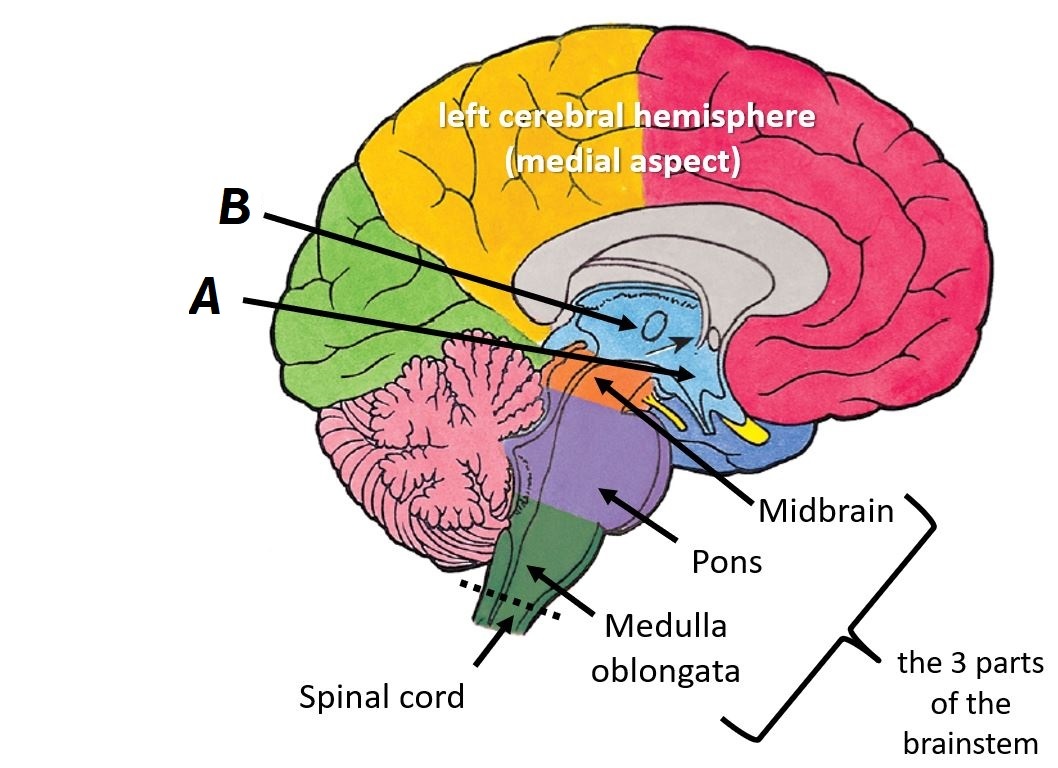

Name structures A and B

A - Hypothalamus

B - Thalamus